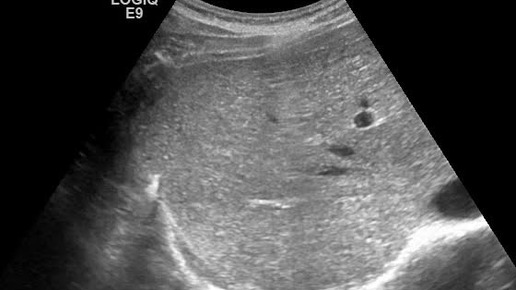

Видео к статье: "Свободная жидкость в брюшной полости"https://dzen.ru/a/Z-1KdOK-KyrjRiGF

Ультразвуковые находки от врача УЗД Зорина Я.П.